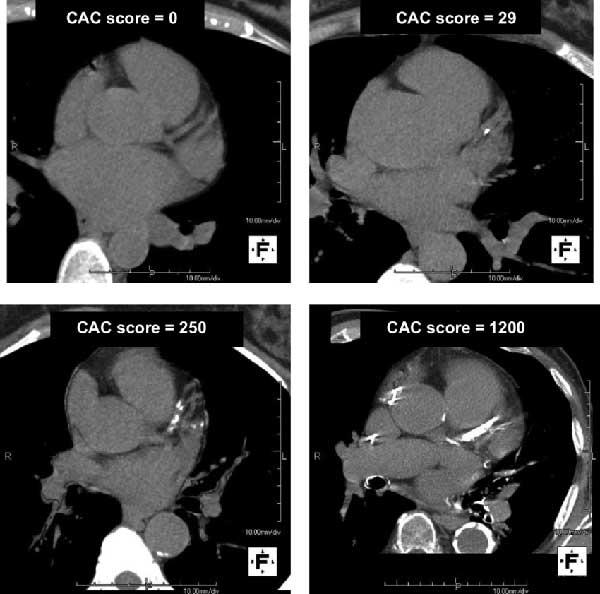

Your calcium test score tells how much calcium is in your coronary arteries. If you have calcium in your heart’s arteries, the computer will create a calcium score that estimates the extent of coronary artery disease. Your calcium test score can range from zero to more than 1,000.

Anything above zero means there’s some evidence of coronary artery disease (CAD).

Higher scores indicate that you could be at risk for a heart attack. Score cutoffs are:

- 100 or less (mild proof of coronary artery disease).

- Up to 400 (moderate amount of proof that you have CAD).

- Above 400 (strong proof of CAD).

What is the normal calcium score?

A normal calcium test score is zero. Healthcare providers also call this a negative scan because it didn’t find any calcification in your heart’s arteries. With this score, you have a very low risk of having a heart attack in the next two to five years. However, keep in mind that your provider will look at your other risk factors for heart disease, as well.